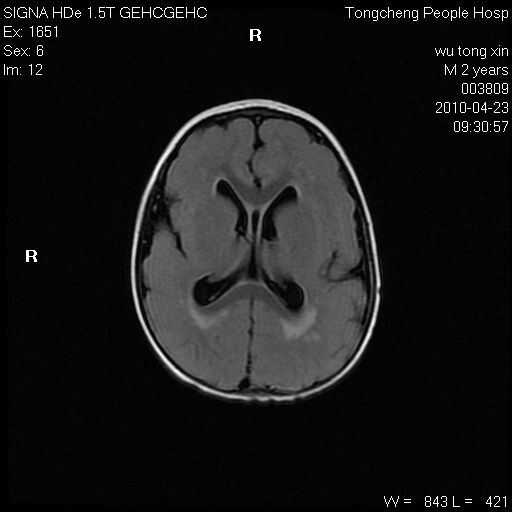

以下是引用赵物学在2010-4-25 12:43:00的发言:[br]巨脑回[br]侧脑室后角低密度影考虑hie或肾上腺脑白质营养不良?[br][br][本贴已被 赵物学 于 2010-4-25 12:51:28 修改过]

以下是引用gaoxiao在2010-4-25 16:54:00的发言:[br]巨脑回畸形。脑白质髓鞘化不良

以下是引用pujunzhi在2010-4-25 21:35:00的发言:[br]考虑 1双侧大脑皮质发育不良 2轻度脑积水 3双侧脑室后角旁片状长t1长t2信号,需继续观察,因为正常小儿此处脑白质的髓鞘化时间可以延迟到4-6岁,才显示正常。